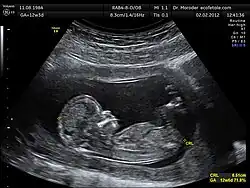

Crown-rump length (CRL) is the measurement of the length of human embryos and fetuses from the top of the head (crown) to the bottom of the buttocks (rump). It is typically determined from ultrasound imagery and can be used to estimate gestational age.

The embryo and fetus float in the amniotic fluid inside the uterus of the mother usually in a curved posture resembling the letter C. The measurement can actually vary slightly if the fetus is temporarily stretching (straightening) its body. The measurement needs to be in the natural state with an unstretched body which is actually C shaped. The measurement of CRL is useful in determining the gestational age (menstrual age starting from the first day of the last menstrual period) and thus the expected date of delivery (EDD). Different human fetuses grow at different rates and thus the gestational age is an approximation. Recent evidence has indicated that CRL growth (and thus the approximation of gestational age) may be influenced by maternal factors such as age, smoking, and folic acid intake. Early in pregnancy gestational age 8 weeks, it is accurate within about +/- 5 days but later in pregnancy, due to different growth rates, the accuracy is lower. In that situation, other parameters can be used in addition to CRL. The length of the umbilical cord is approximately equal to the CRL throughout pregnancy.